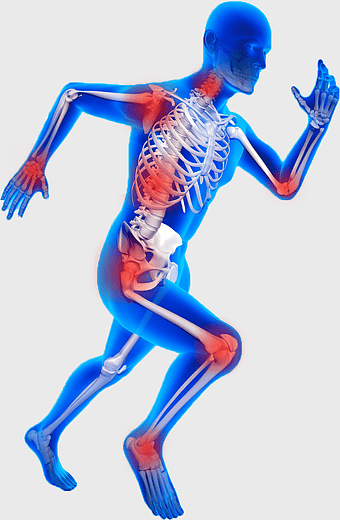

knee pain sports injury, physical therapy for athletes, human knee bones anatomy, joint focus in running, skeletal health in sports, musculoskeletal injury prevention, running biomechanics analysis -

blue man running anatomy, elastic therapeutic tape for pain, True Balance Chiropractic running therapy, human body joint pain, athletic injury recovery, skeletal health visual, mobility rehabilitation physics -